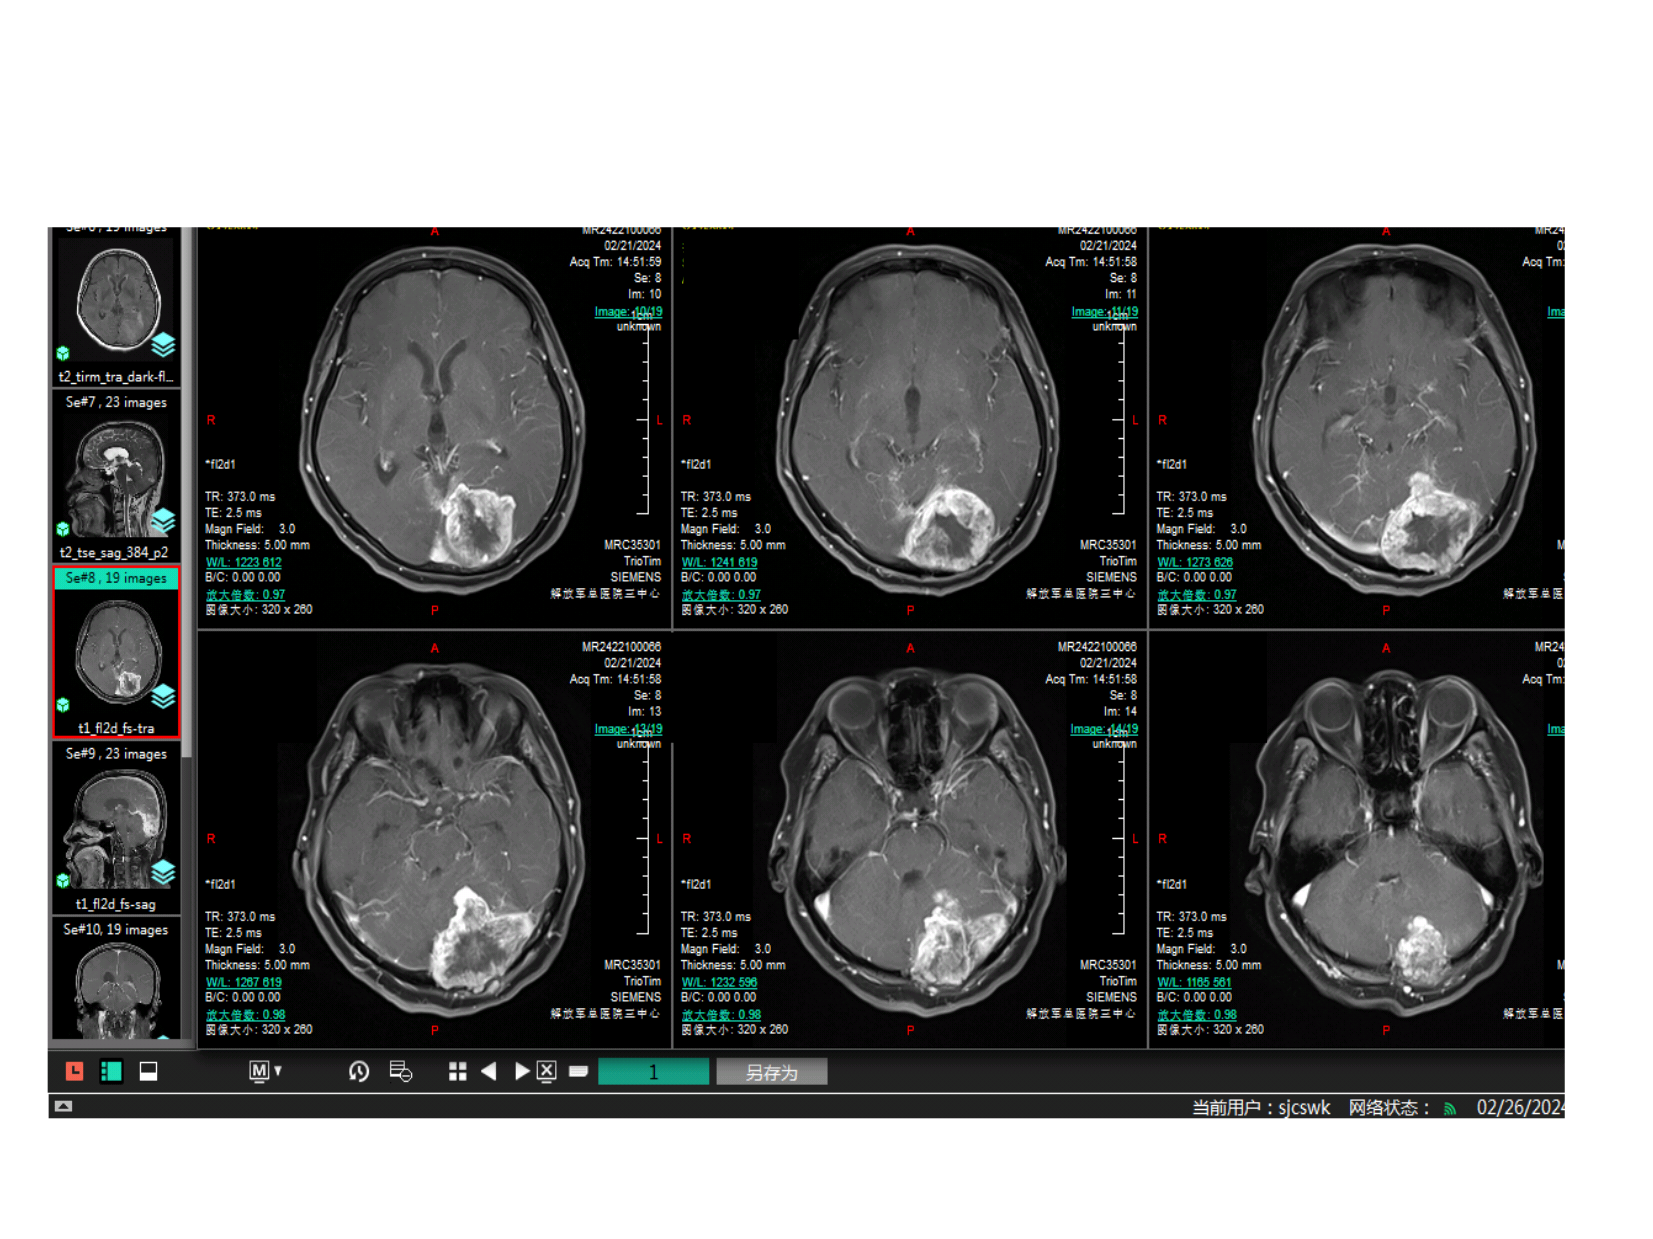

CT为等密度占位,内有低密度改变,可能为坏死灶。肿瘤边缘清楚。

增强后可见肿瘤穿透小脑幕,幕上下均有肿瘤

肿瘤并未穿过大脑镰到对侧,SSS后1/3通畅。

肿瘤并未穿过大脑镰到对侧,SSS后1/3通畅。周边脑组织水肿不明显明显。证明蛛网膜界面尚完整。